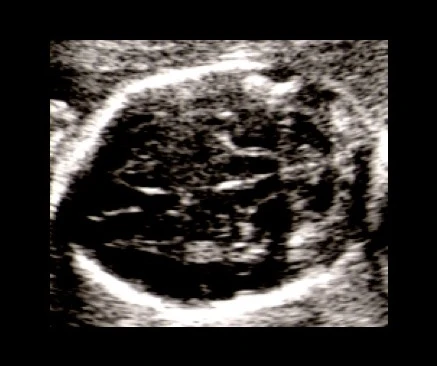

Ultrassom do crânio fetal em caso de mielomeningocele

Ultrassom

Crânio fetal · Mielomeningocele

Clique nos botões acima para alternar entre o ultrassom normal, o sinal da banana (cerebelo) e o sinal do limão (formato do crânio).